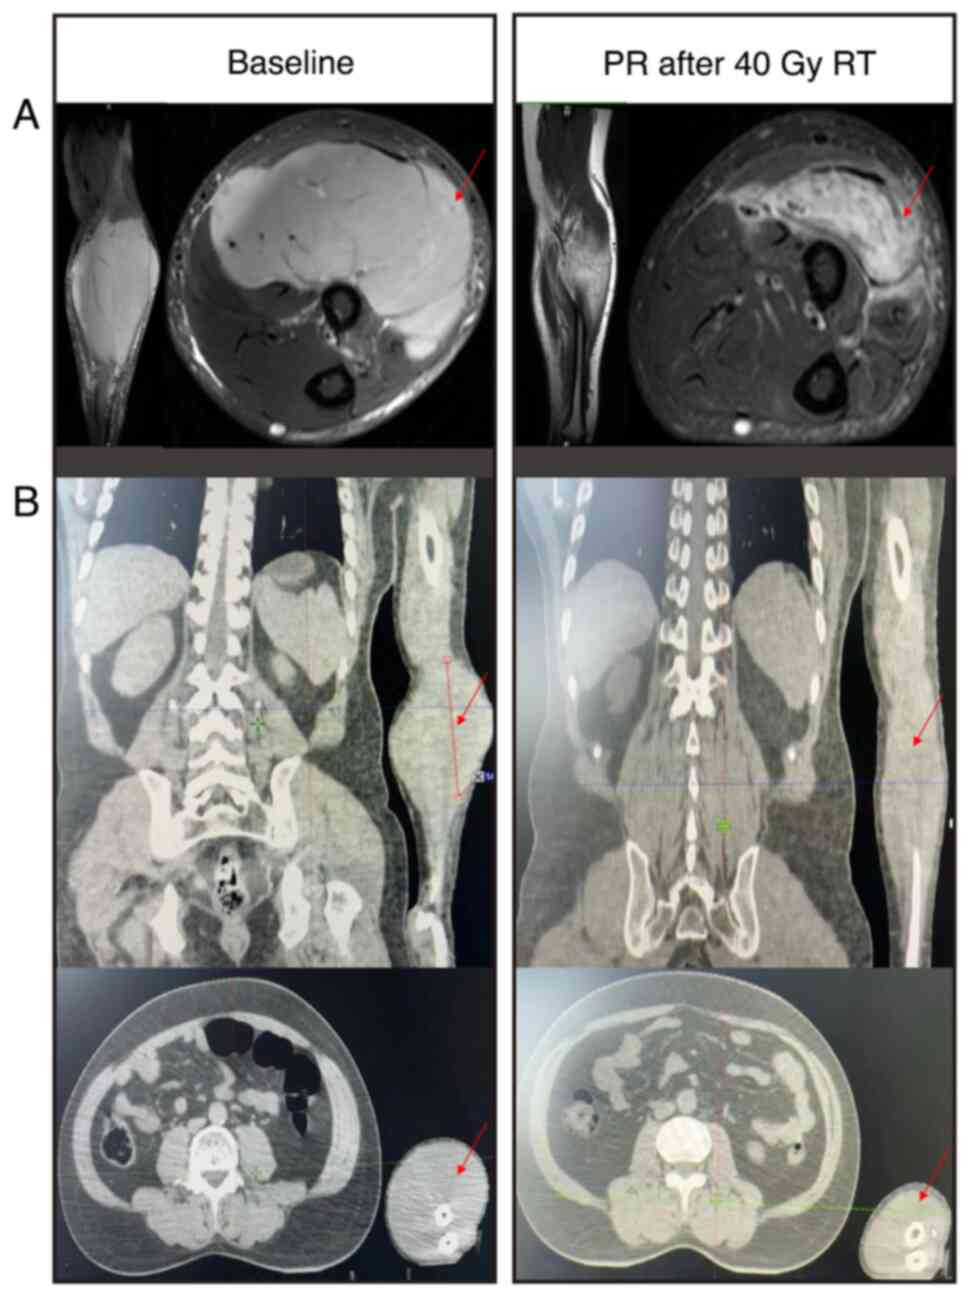

Primary gingival diffuse large B‑cell lymphoma (DLBCL) with muscle invasion is rare and accounts for ~0.5% of all reported cases of extranodal lymphoma. The present study describes the case of a 49‑year‑old man that initially presented at Yingshan County People's Hospital (Nanchong, China) in August 2017 with a chief complaint of tenderness and swelling of the jaw. Computed tomography revealed a mass in the gingiva, and enlarged lymph nodes in the cervical, mediastinal and gastro‑hepatic ligaments. Histological examination indicated the gingival mass was a DLBCL, which was positive for CD20, BCL‑6, BCL‑2, C‑MYC and MUM1. The patient received three lines of anti‑neoplastic therapy (R‑CHOP, R‑CHOEP and SYHX1903) and achieved stable disease for 6 years. Subsequently, the patient experienced trauma in the left forearm due to a car accident and the subsequent color Doppler imaging led to a diagnosis of muscular hematoma; however, magnetic resonance imaging and biopsy of the forearm muscle confirmed DLBCL invasion. Due to the patient suffering from heart failure after the third line of the previous chemotherapy, palliative radiotherapy was administered to the left forearm, and the patient achieved a partial response. In conclusion, primary gingival DLBCL with muscle invasion is rare and easily misdiagnosed, and individualized treatment should be considered for these complex cases.

Figure 3